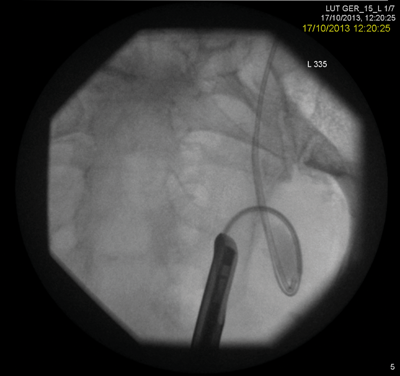

A known male stone former with significant cardiovascular co-morbidity and a history of a low anterior resection history presented with a large left lower ureteric stone having undergone a failed ureteroscopy by another surgeon with resection of the ureteric orifice.

A rendezvous procedure was performed in the supine oblique position. The radiologist punctured the non-dilated kidney, feeding a wire antegradely to the bladder, allowing subsequent ureteroscopy and stone clearance.

Multiple failed attempts at ureteroscopic or percutaneous access do not help the doctor-patient relationship and can potentially put the patient at unnecessary risk when comorbidity is present. The Rendezvous procedure should not be forgotten as a ‘one stop’ method of dealing with ureteric obstruction. A combined antegrade and retrograde approach may decrease the number of separate interventions required to successfully cross a difficult stricture.